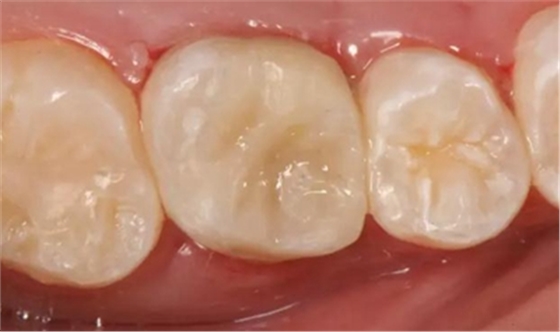

最后附昨天備牙,今日戴牙的一個美塑嵌體。